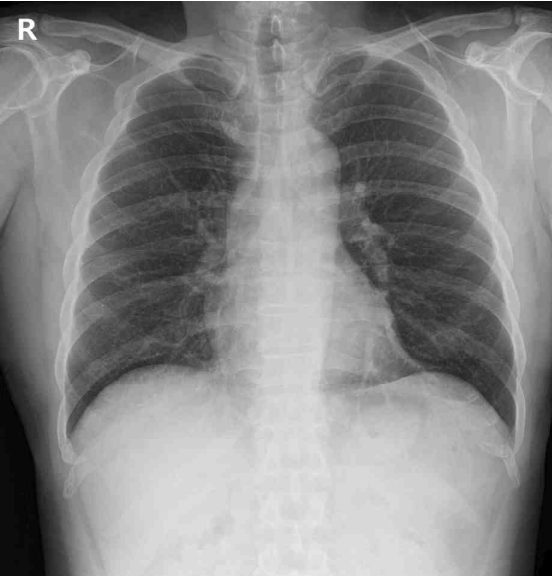

54세 남자가 1시간 전부터 가슴이 아파서 응급실에 왔다. 15년 전부터 혈압강하제를 복용하고 있다. 혈압 110/60 mmHg, 맥박 92/분, 호흡 20/분, 체온 36.8°C이다. 심음과 호흡음은 정상이다. 나이트로글리세린을 혀 밑으로 투약했으나 통증은 지속되었다. 검사 결과는 다음과 같다. 가슴 X선사진과 심전도이다. 치료는?

CXR: No remarkable findings